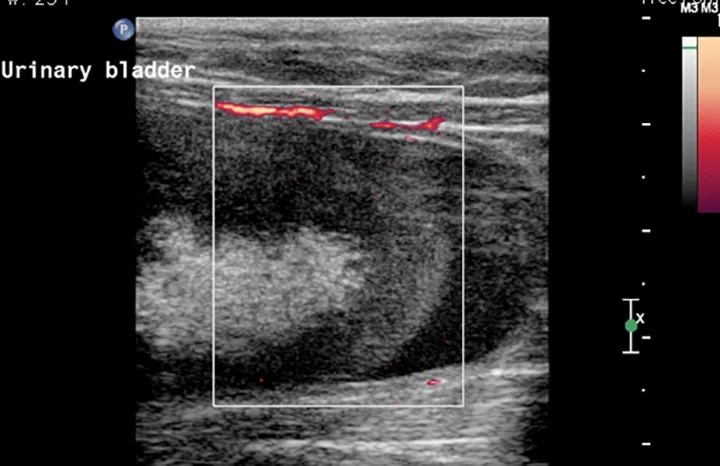

Figure 2. A large echogenic structure is present within the urinary bladder. Power Doppler image shows that there is no blood supply to this material within the urinary bladder.

Additional diagnostic tests included abdominal ultrasound (Figure 2) and computed tomography (CT) scan with IV contrast media (Figure 3).

1. Urinary bladder hematoma admixed with sandy calculi was suspected. The structure had no blood flow, which made a neoplastic process less likely. Given the findings of the previous abdominal FAST scan, a urinary bladder hematoma was the top differential.

2. The choice was made to surgically remove the urinary bladder hematoma via cystotomy. The source of the blood was thought to be renal because of the size and severity of the clot. Ivan was likely continuing to bleed into his urinary tract over the course of his stay because he continued to exhibit hematuria and his PCV continued to drop. This suggested that a moderate-sized bladder after the perineal urethrostomy was actually an organized blood clot, not urine, because there is minimal bleeding from the urinary tract after a perineal urethrostomy. Another option would have been to try to dissolve the clot with tissue plasminogen activator, as is done in humans6; however, given the size of the clot, surgery was decided to be the better option.